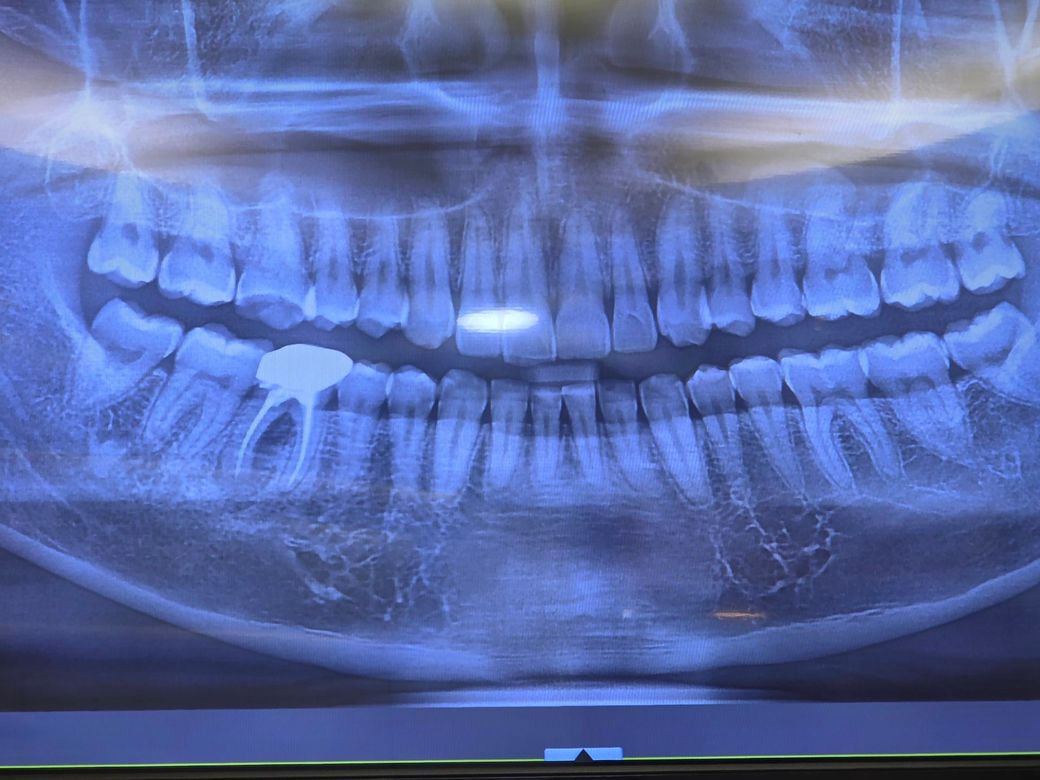

잇몸 누공 발치 말고는 답이없을까요..

크라운 치료받은 치아 잇몸에 누공이 발생하였고

치과에서 발치후 임플란트 치료 제안 받았습니다.

그리고 부비동에 염증 가능성있다는 이야기도 들었습니다.

크라운 한 치아 즉 오른쪽 아래 어금니입니다. 이정도면 발치 말고는 다른 방법이 없을 것으로 보입니다. 잇몸뼈 염증이 심한 상태입니다. 부비동 염증은 위쪽 치아와 관련된 것으로 현재 증상 없으면 그냥 두어도 됩니다.

치성원인으로 상악동까지 염증이 퍼졌다면 치아에 대한 처치 + 상악동 염증 제거를 위한 상악동 근치술 두가지 다 진행해야 합니다. 대학병원 구강외과 가보시기 바랍니다.